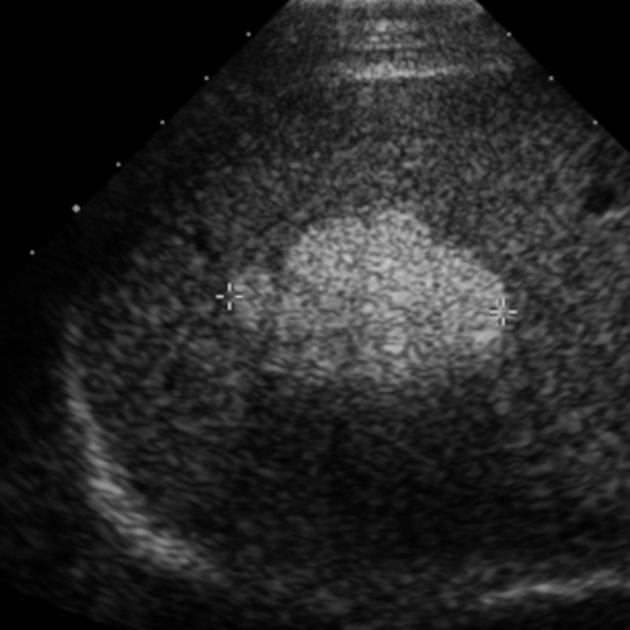

400

What is the most likely diagnosis in an asymptomatic patient?

Hemangioma